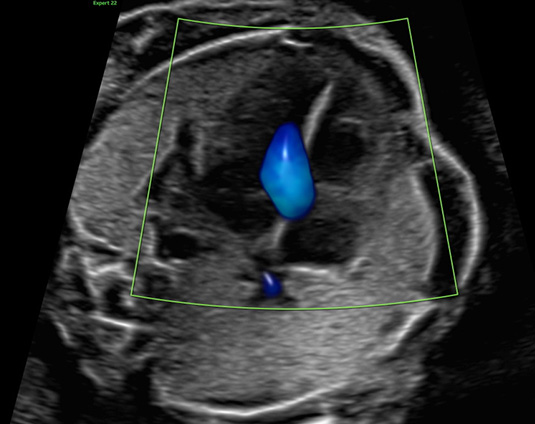

Die Herzechokardiografie ist eine ausführliche Untersuchung des kindlichen Herzens, in der die Entwicklung und die Funktion beurteilt werden. Der optimale Zeitpunkt für die Untersuchung ist die 20.-22. Schwangerschaftswoche. Es ist aber auch möglich im Rahmen der frühen Fehlbildungsdiagnostik (Ersttrimesterscreening) eine detaillierte Herzbeurteilung durchzuführen. Beurteilt werden die Lage und Größe des Herzens, das Aussehen und die Funktion der Herzkammern und Herzklappen sowie der zuführenden Venen und abgehenden Gefäße. Durch die gezielte Echokardiographie mit Farbdoppler, gepulstem Doppler und M-Mode lässt sich der Großteil aller angeborenen Herzfehler erkennen. Die Voraussetzungen hierzu sind eine spezielle Ausbildung und Erfahrung des Untersuchers und eine hohe Qualität des Ultraschallgerätes.